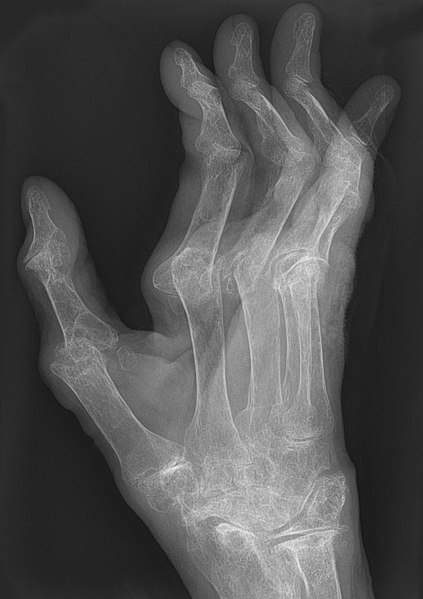

Arthritic changes – Arthritis is related to a condition of painful joints due to inflammation or swelling. A type of arthritis is rheumatoid arthritis, it is an autoimmune disease where the immune system attacks the joints, starting with the lining of joints. Rheumatoid arthritis is heavily related to lung problems, about 80% of arthritic patients have lung-related issues, making it the second leading cause of death with rheumatoid arthritis patients. Rheumatoid arthritis caused lung problems are most commonly extra-articular i.e., outside of the joints and involves pulmonary nodules; damage to the lung airways, pleural effusion and interstitial lung disease. In rheumatoid arthritis associated interstitial lung disease the auto-immune system gets over active and attacks the lungs and causes scarring. With time, the scarring build-up leads to difficulty breathing and reduced lung function.